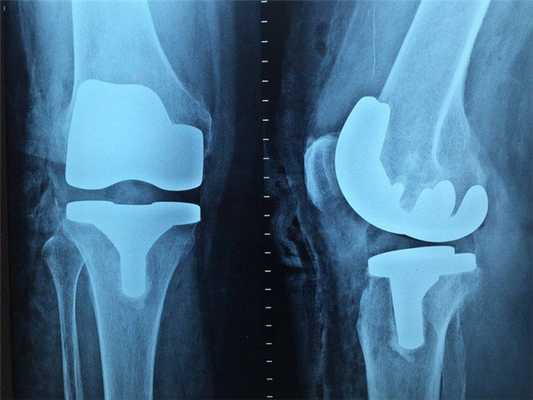

Наиболее эффективно будет проводить рентгенографию при повреждениях костей, суставов и зубов.

Компьютерная томография (КТ)

Компьютерная томография тоже осуществляется по принципу рентгенографии, но в результате врач получает не плоскую двухмерную картинку, а трёхмерное изображение. Это достигается путём одновременного создания большого числа снимков, которые собираются в единое изображение. Датчики компьютерного томографа обладают высокой чувствительностью и различают огромное количество оттенков, поэтому врач может детально рассмотреть все кости и органы пациента. Дополнительно повысить качество изображения можно, если ввести пациенту специальное вещество, так называемый “контраст”. Контраст помогает отличить здоровые ткани от изменённых и обнаружить аномальные структуры в организме, а также даёт возможность детально изучить состояние сосудов. КТ с контрастом назначают не в каждом случае, часто достаточно простой компьютерной томографии.

КТ делается быстро, с его помощью проводить скрининг на рак лёгких. Также можно использовать компьютерную томографию непосредственно во время проведения хирургических операций.

Недостатками КТ можно считать высокую лучевую нагрузку на пациента. Поэтому КТ не назначают беременным женщинам, детям и пациентам с избыточным весом (более 200 килограмм).